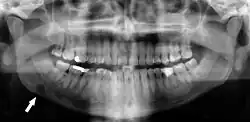

Panoramic radiograph showing horizontally impacted lower wisdom teeth.

Minimally-displaced fracture in right mandibular. Arrow marks fracture, root canal on central incisor, teeth to the left of fracture do not touch

Panoramic radiograph showing Stafne defect (arrowed).